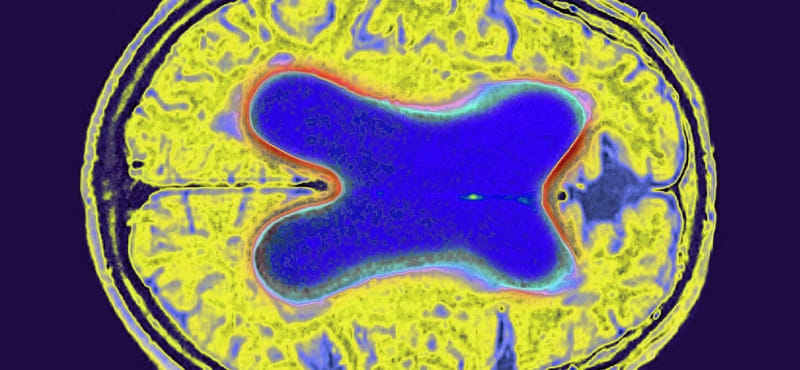

Erős Alzheimer-védelem alatt állhat annak az agya, aki legalább két nyelven tud

Bár a két nyelv ismerete és használata nem óv meg a demenciától, azonban védelmet jelenthet az agytérfogat-csökkenéssel szemben Alzheimer-kór esetén – állítják kanadai kutatók.